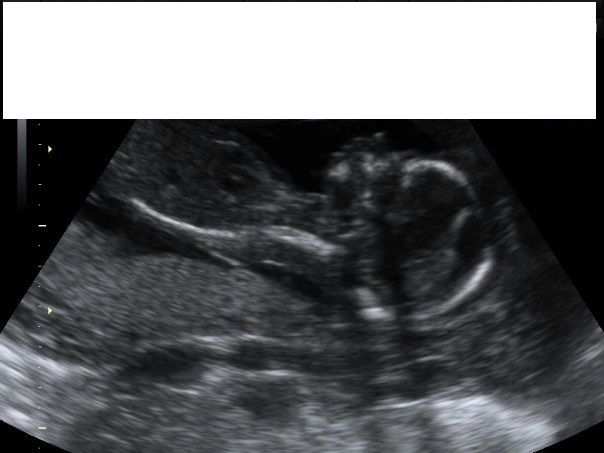

I am looking for head/profile pictures to compare to my 18 week u/s pics of my current baby. I am really hoping for a boy, but the pic looks like a girl to me... just wanting to see pics of other baby boys to get some hope!!